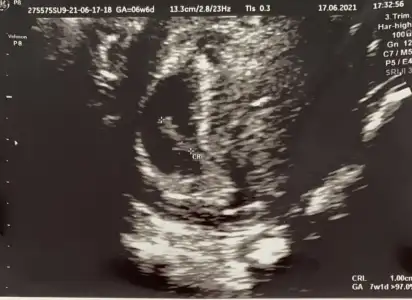

Benim de 7 Haftalık karından ultrason cinsiyet yorumlayabilirseniz sevinirimEvet ramziye göre erkek![]()

Benim de 7 Haftalık karından ultrason cinsiyet yorumlayabilirseniz sevinirim![]()

Ramziye göre kızBenim de 7 Haftalık karından ultrason cinsiyet yorumlayabilirseniz sevinirim![]()